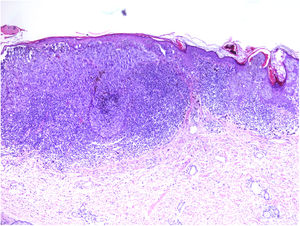

TILs should be classified as absent (not identified or identified but not in contact with the tumor), brisk (infiltration of the entire base of the tumor [Fig. 1) or diffuse infiltration of the tumor) (Fig. 2), or nonbrisk (focal infiltration or infiltration of part of the base of the tumor).

The pathology report should also specify whether the infiltrate is intratumoral, peritumoral, or both.